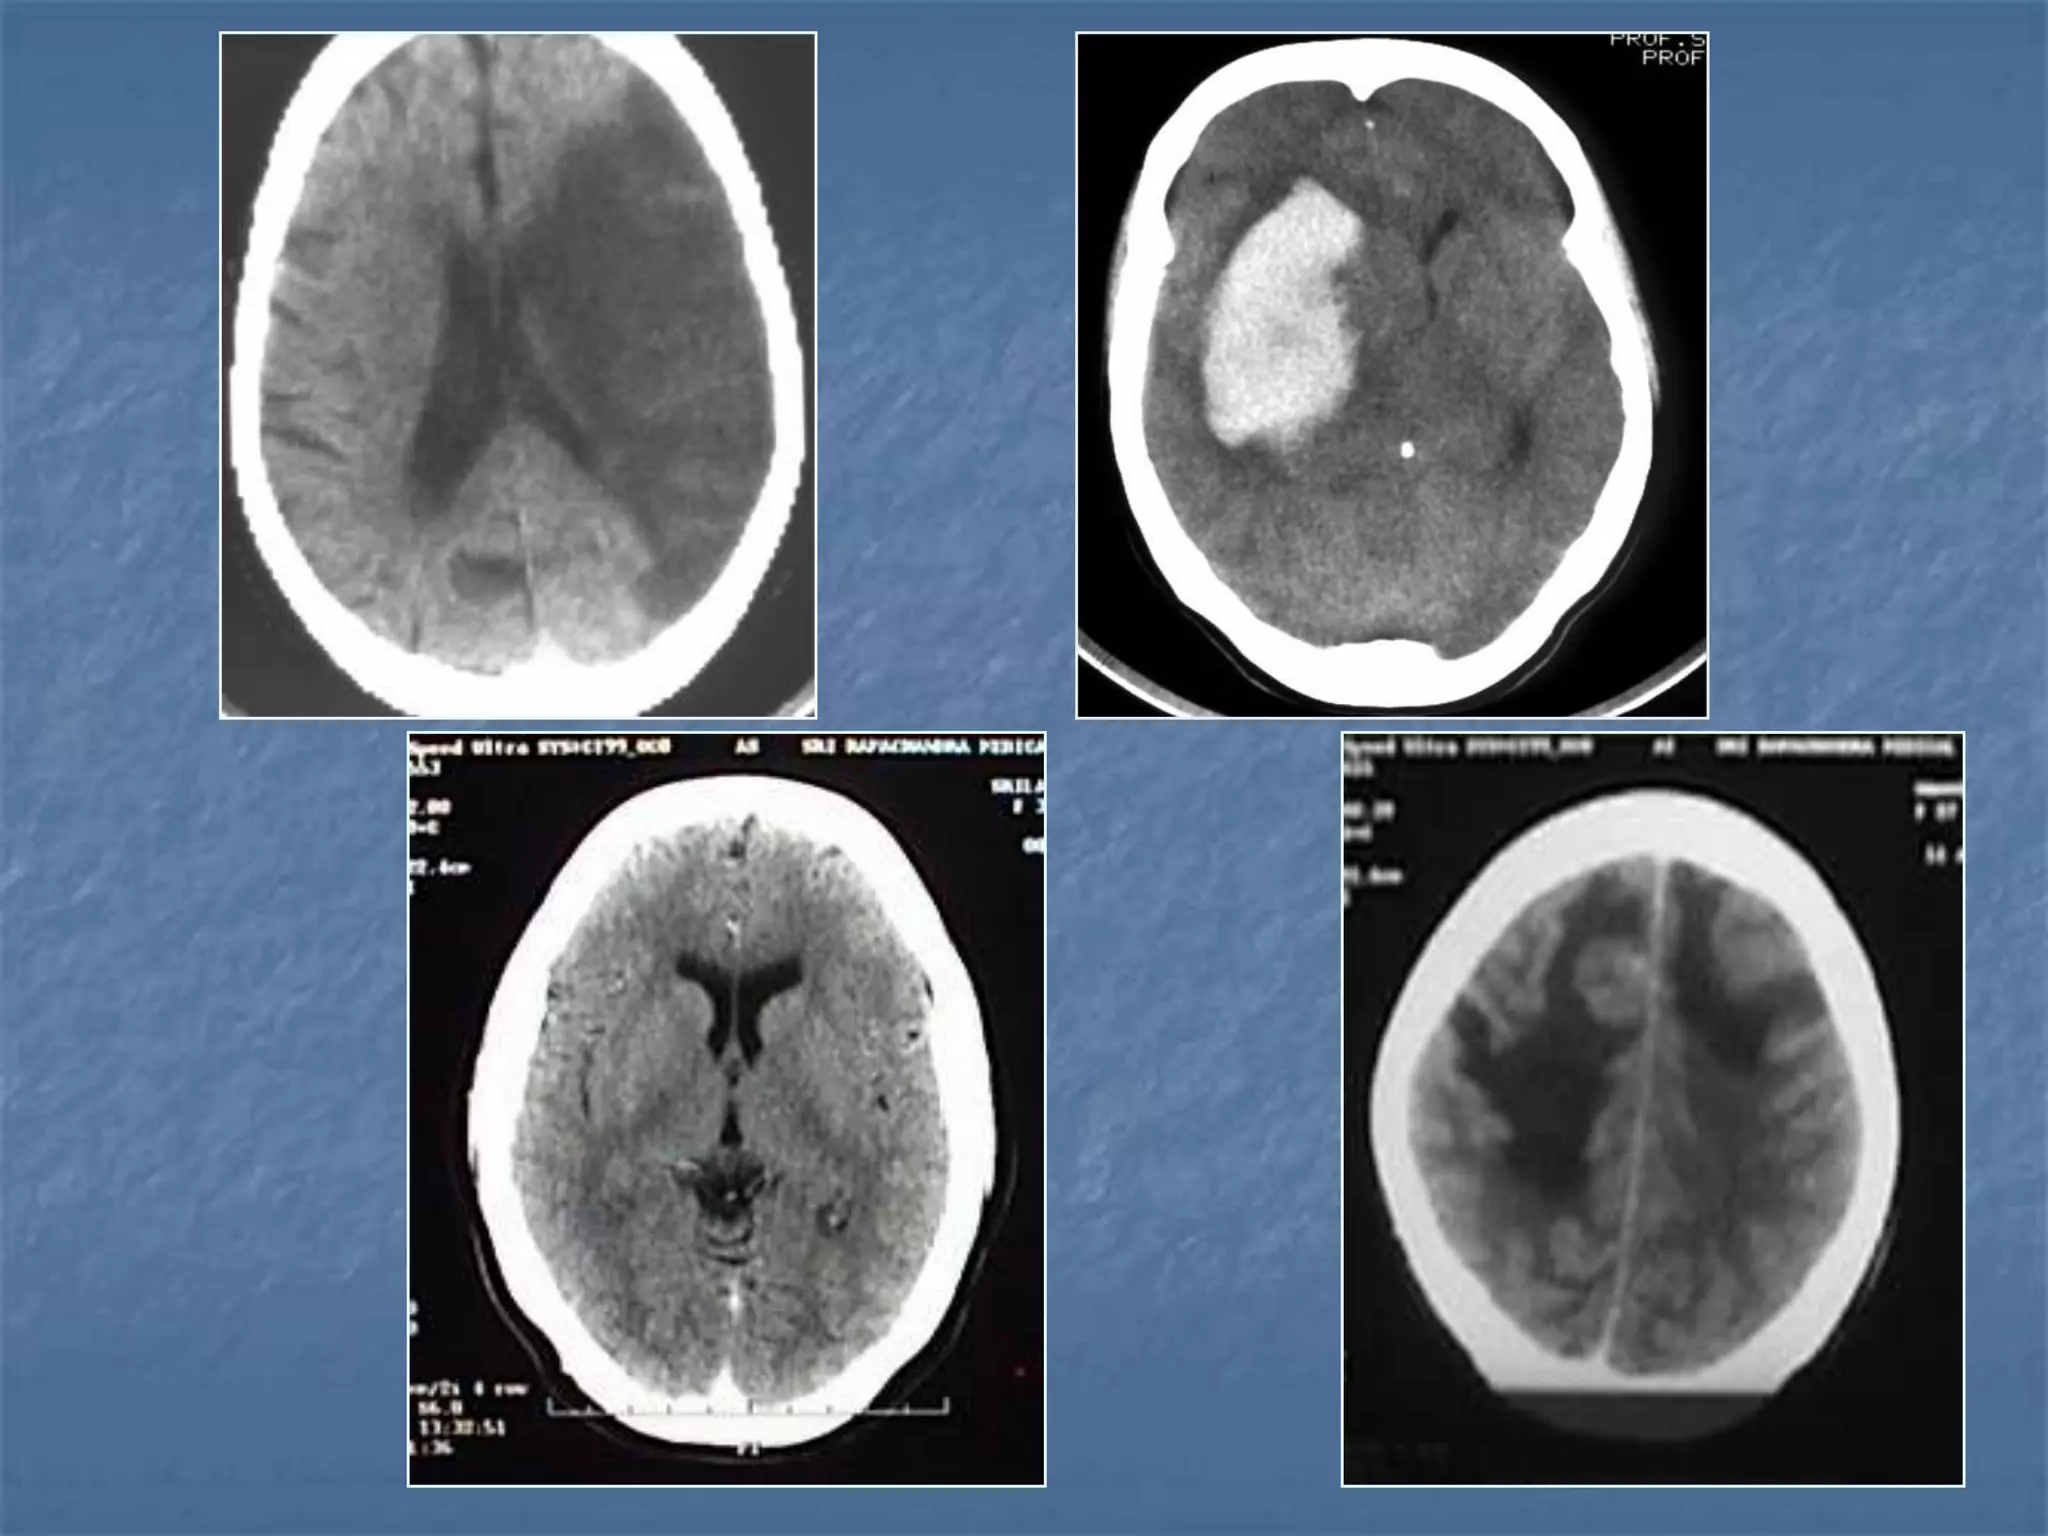

Hypertensive Hemorrhage

 Hypertensive hemorrhage accounts for

approximately 70-90% of non-traumatic primary

intracerebral hemorrhages. It is commonly due to

vasculopathy involving deep penetrating arteries

of the brain. Hypertensive hemorrhage has a

predilection for deep structures including the

thalamus, pons, cerebellum, and basal ganglia,

particularly the putamen and external capsule.

Thus, it often appears as a high-density

hemorrhage in the region of the basal ganglia.

Blood may extend into the ventricular system.

Intraventricular extension of the hematoma is

associated with a poor prognosis.

Haemorrhagic StrokeEtiology

 Hypertension

 Vascular malformation

 Aneurysm

 Trauma

 Amyloid angiopathy

 Tumor

 Coagulopathy

 Hemorrhages can occur in the intraparenchymal,

subarachnoid, intraventricular, subdural and

extradural spaces.

 Location of hypertensive hemorrhage:

Putamen, external capsule, thalamus, pons,

cerebellum, subcortical white matter